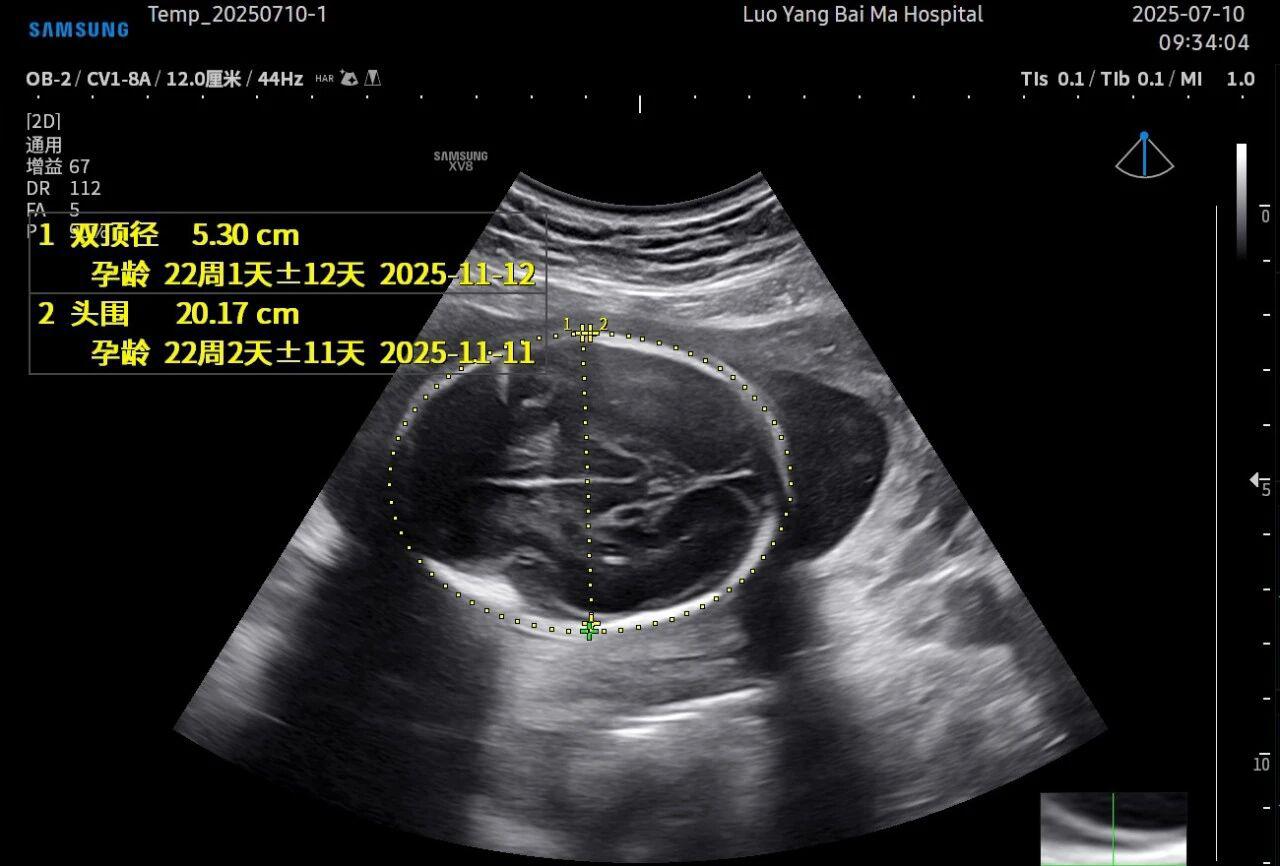

3. AI智能辅助,提升诊断效率与客观性

这是5D技术的核心优势之一。系统内置了强大的智能化大数据分析功能和AI辅助诊断工具。例如,在进行胎儿颈项透明层(NT)测量、胎儿长骨(LB)测量等关键生物学指标评估时,5D智能系统可以自动识别解剖层面、智能勾勒测量范围并进行计算。这不仅大大缩短了检查时间,更重要的是,它通过标准化的智能算法减少了因人为操作可能产生的误差,使诊断结果更加客观、可靠。